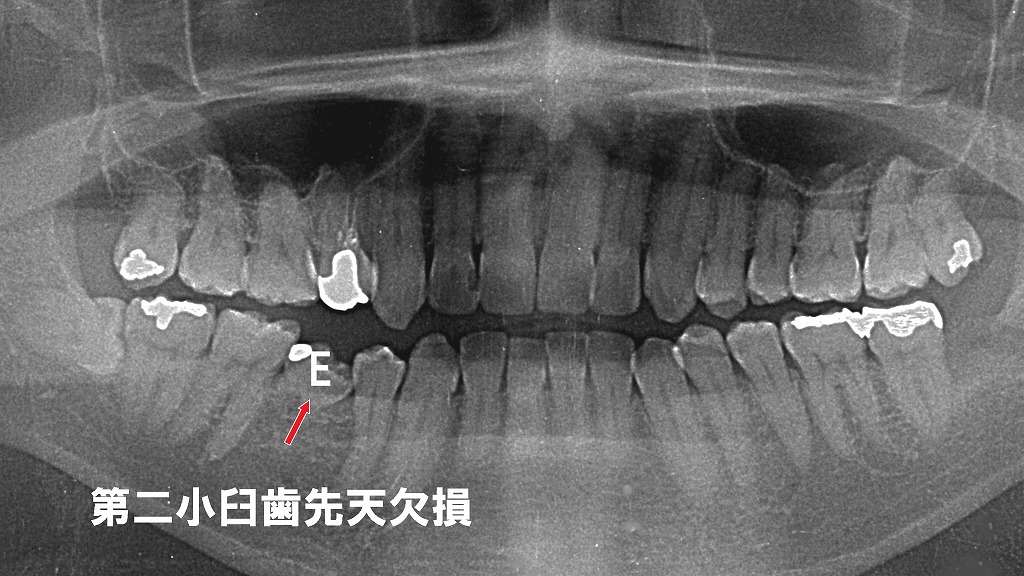

右下の乳歯 E(第2乳臼歯) が抜けそうになっていますが、その後継永久歯である 第二小臼歯が先天的に欠損 しているため、永久歯の萌出が起こらず、歯列にすき間や咬み合わせの乱れが生じる可能性があります。

小児期に適切なタイミングで咬合管理や矯正治療を行わないと、前歯のスペース、奥歯の咬合崩壊など、成人後により複雑な不正咬合へ進むことがあります。

左右の第二小臼歯が先天欠損しているため、乳歯Eにブラケットを装着し、咬合と歯列のバランスを整える矯正治療を行っています。乳歯を歯列の一部として活用しながら、スペース管理と乳歯Eが脱落した場合の咬合を考慮した治療計画が必要になります。